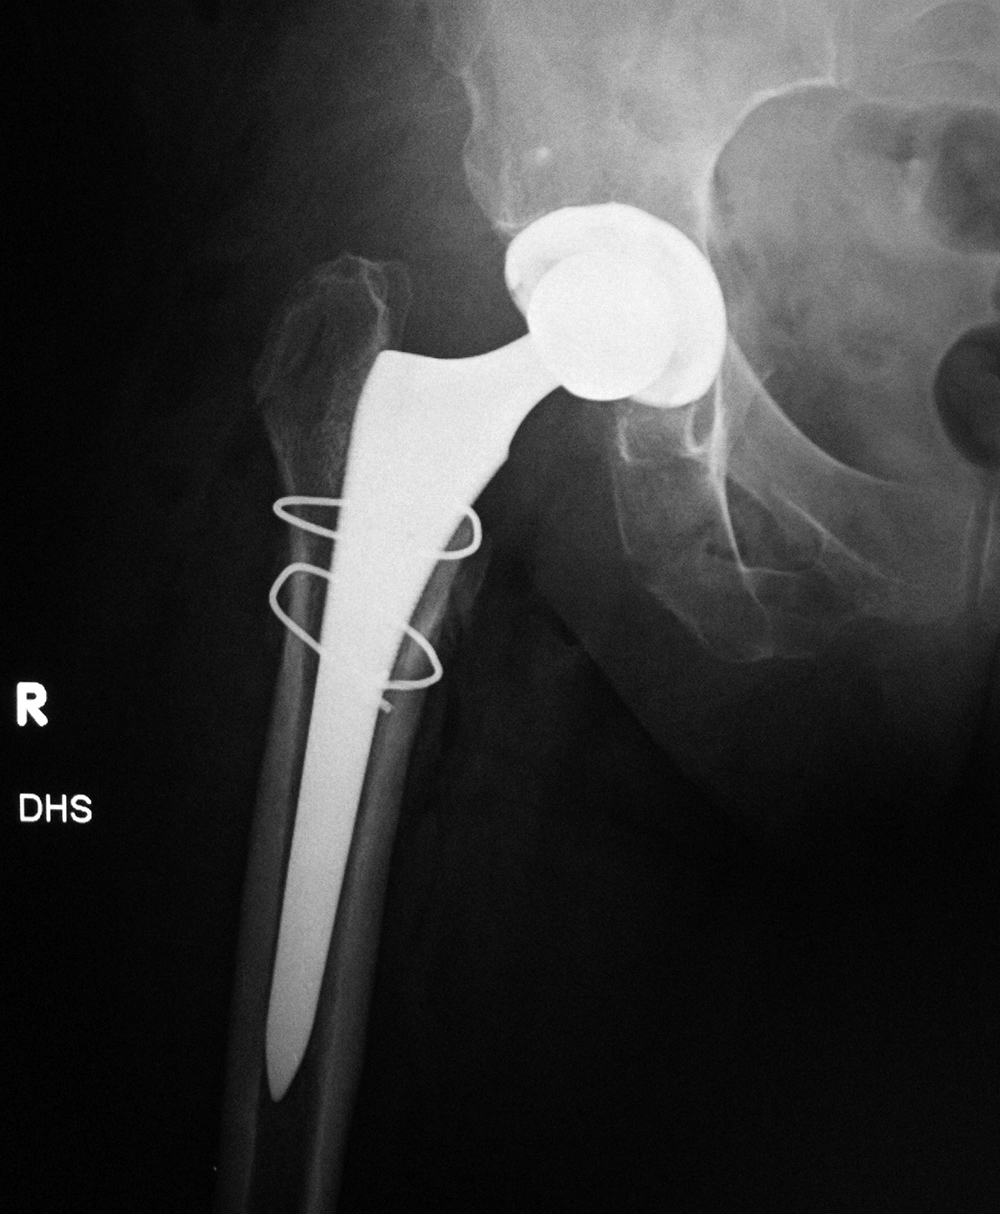

| Bipolar hemiarthroplasty with claw plate and cables

| 78 year-old woman with prior bipolar hemiarthroplasty; presently treated with claw plate and cables for intertrochanteric fracture.

|